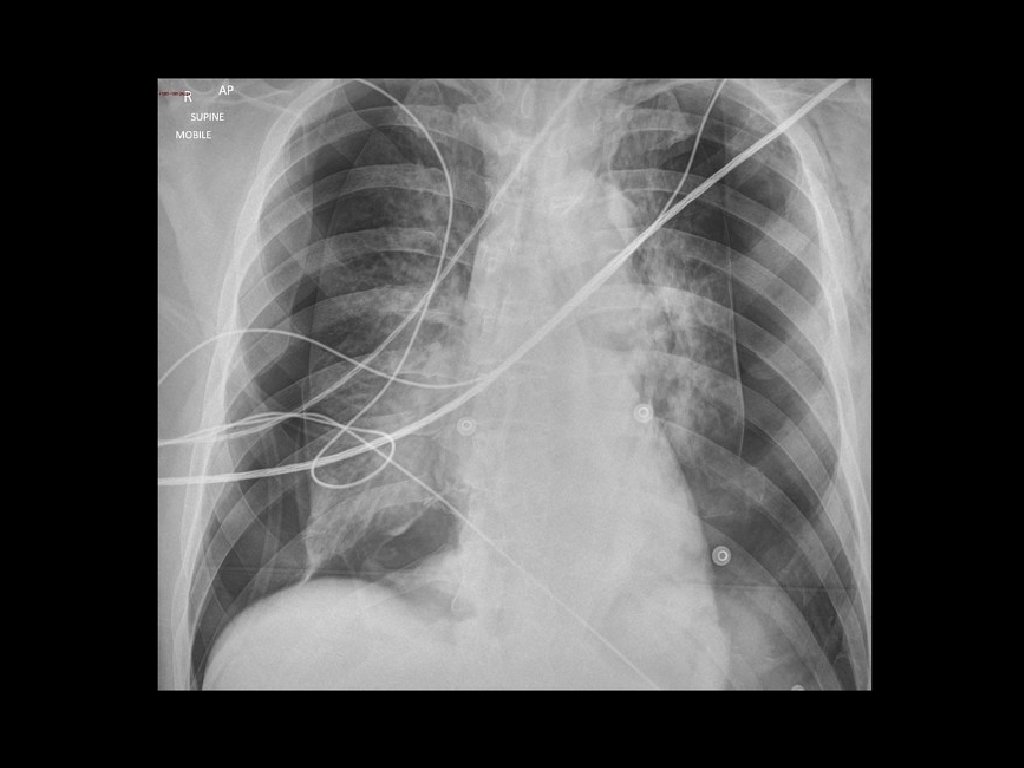

Imaging: • CXR is commonly performed in the evaluation of ED patients with chest pain. • Most patients with ACS have a normal CXR. • Useful to exclude other conditions such as pneumonia and pneumothorax.

Tension Pneumothorax • Can occur for many reasons including iatrogenic (e. g. from central lines). • Shock and respiratory symptoms due to pneumothorax compressing the mediastinum, resulting in decreased venous return to the heart. • Often secondary to thoracic trauma.

• It can also caused by a simple spontaneous pneumothorax progressing to tension pneumothorax. • Diagnosis is clinical, Don’t wait for the X-ray to make the diagnosis. • Treat with needle decompression while preparing for ED Thoracostomy.